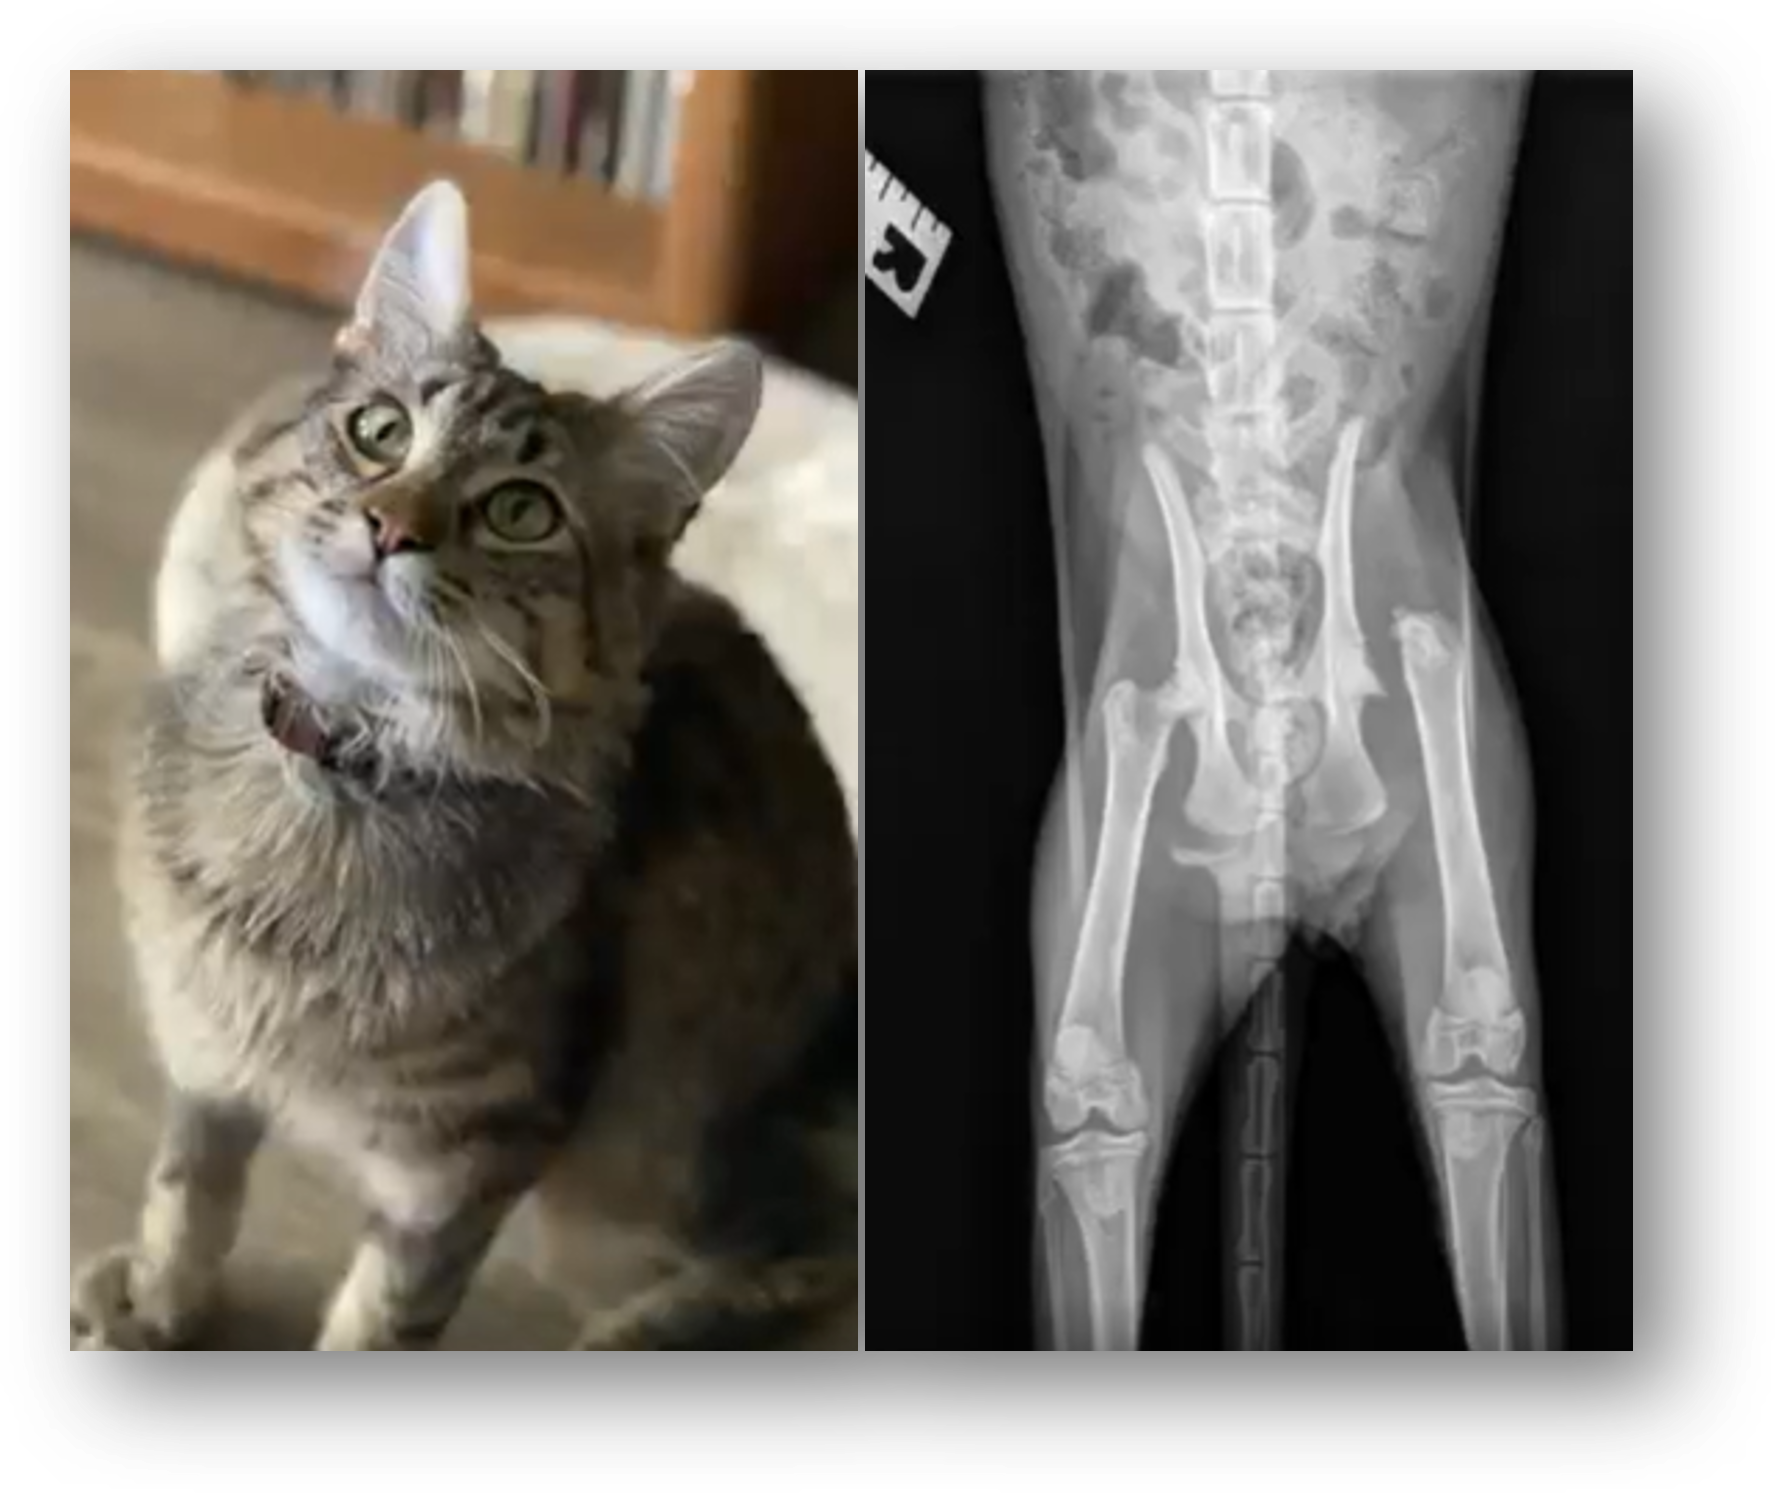

Sassy was wandering the streets and made her way into a rural shelter that, unfortunately, was full. They noticed Sassy had striking, bowed legs, and contacted the Idaho Humane Society to see if we could take her in and provide medical care.

Our veterinarians discovered that Sassy had painful birth defects affecting both of her front legs and needed surgery. Thankfully, her procedure went well, and she went into a foster home for rest, recovery, and lots of love. Watch video…